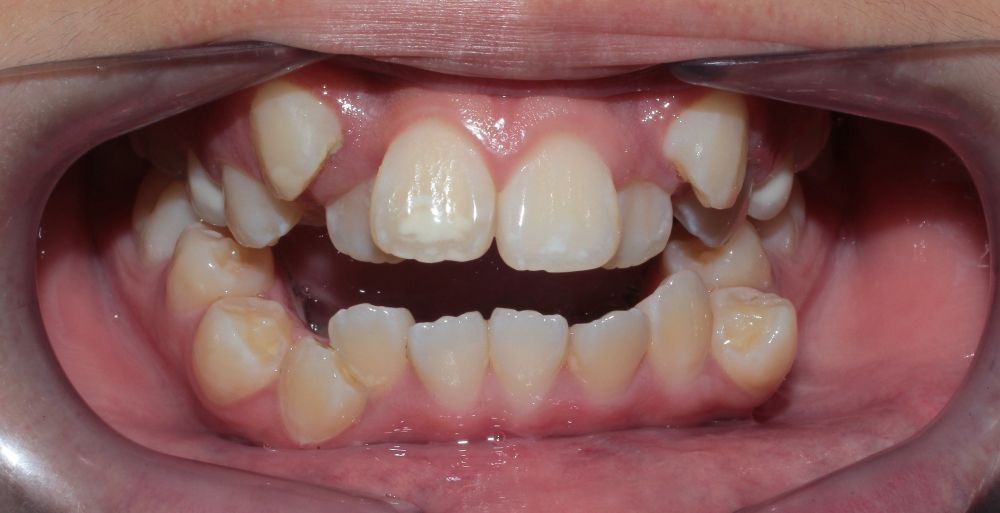

Teeth/Bone Red Flags

Full mouth of baby teeth with no spacing

Premature loss of baby molar

Posterior cross-bite

Airway and jaw issues develop gradually, in ways that seem normal at first. Mouth breathing, crowded teeth, a recessed chin—these signs feel subtle because they happen slowly.

Mouth Breathing/Thumb Sucking

Tongue will not rest on upper jawbone and us unable to guide its growth

Under-developed V-Shaped upper arch

Case Study 1

Lower jaw growth → Improved airway and neck posture

“His upper teeth are too protruding. How can we fix this without making him suffer?”

Clinical observation

It is the under-developed lower jaw that is making the upper jaw appear protruded.